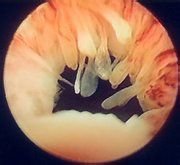

折叠宫颈

检查目的:观察宫颈上有没有肿物、溃疡、糜烂、息肉,宫颈大小是否正常,表面是否光滑,质地是否过硬,有无子宫脱垂。正常宫颈:周边隆起,中间有孔。未产妇呈圆形,已产妇呈“一”字形,质韧,肉红色,表面光滑。如果要做宫颈防癌涂片检查,医生会在此时采取标本。

虽然如此,女性每年进行一次宫颈涂片检查,就能及时发现宫颈病变。采用电子阴道镜检查对宫颈炎的病变程度及发现早期恶变,有一定的诊断作用。治疗手段有效、便捷。